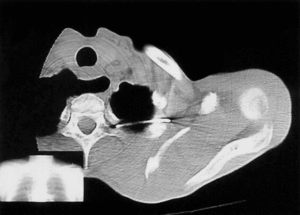

En la radiografía simple del hombro se apreció migración intratorácica de una aguja de Kirschner, procedente de la osteosíntesis realizada en la articulación acromioclavicular izquierda (fig. 1). El paciente fue ingresado para completar el estudio. Durante su ingreso se realizó tomografía computarizada (TC) con contraste para objetivar el grado de afectación de las estructuras intratorácicas, visualizándose una invasión de la cavidad torácica a través del ápex pulmonar izquierdo, sin neumotórax, lesión medular, vascular o mediastínica acompañantes (fig. 2). El paciente fue valorado por el Servicio de Cirugía Torácica del Hospital, y dado que no había afectación de estructuras neurovasculares y que la migración estaba limitada por el arco posterior de una vértebra torácica, se adoptó una actitud conservadora, realizando un seguimiento evolutivo del paciente.

Figura 2. Imagen de tomografía axial computarizada (TAC) en corte axial que muestra la localización exacta de la aguja migrada. Obsérvese que la migración se encuentra limitada por el arco posterior de una vértebra torácica.